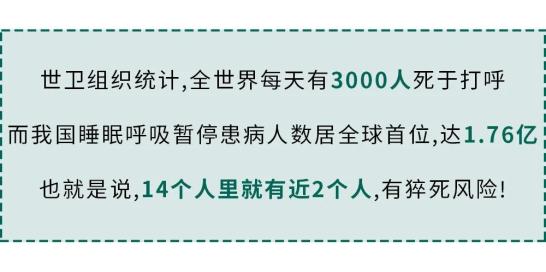

而让我更震惊的是:

泰安一名35岁男子,在睡觉中呼吸暂停,不幸离世。他家人说,他平时身体健康,看不出任何问题。

泰安一名35岁男子,在睡觉中呼吸暂停,不幸离世。他家人说,他平时身体健康,看不出任何问题。 34岁的卢医生,又高又壮。却在一次睡梦中差点断气,找到同事一检查,自己竟然每小时至少呼吸暂停40次,最高70次/小时!

34岁的卢医生,又高又壮。却在一次睡梦中差点断气,找到同事一检查,自己竟然每小时至少呼吸暂停40次,最高70次/小时! 这种病甚至连孩子都不放过。6岁的豪仔晚上睡觉呼吸暂停,最长49秒,一夜505次!他的妈妈每晚都要确认,他是不是还活着。

这种病甚至连孩子都不放过。6岁的豪仔晚上睡觉呼吸暂停,最长49秒,一夜505次!他的妈妈每晚都要确认,他是不是还活着。 打呼猝死,就真切发生在我们身边!看到这,大家可能会有疑问: